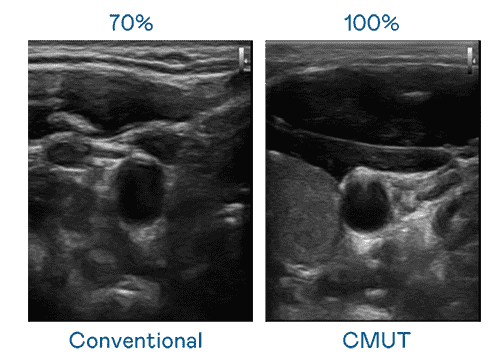

CMUT 技术是一种用电容式微机电元件来产生超音波讯号的技术。。。。与传统 PZT 压电式技术相比,,CMUT 频宽增加 30%,,更宽频的超音波讯号让影像解析度大幅提升,,,是实现高影像品质医疗超音波扫描、、促进精准医疗发展的关键技术。。。

大频宽带来超清晰影像

超音波影像的解析度高低,,首先取决于探头能发出的讯号频宽。。。龙门国际 CMUT 可提供高清晰的超音波讯号,,,,提供高频宽、、、、高灵敏度、、、影像纹理细节更高的超音波影像,,,,协助医护人员缩短影像判读时间及利用精准的医疗影像进行诊断。。。。